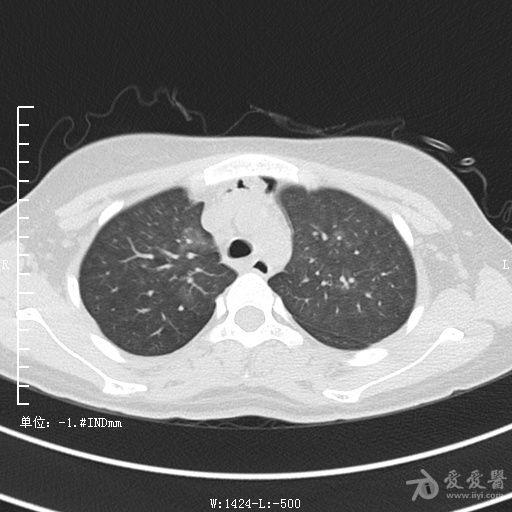

典型支气管扩张及肺水肿CT片

典型支气管扩张肺水肿